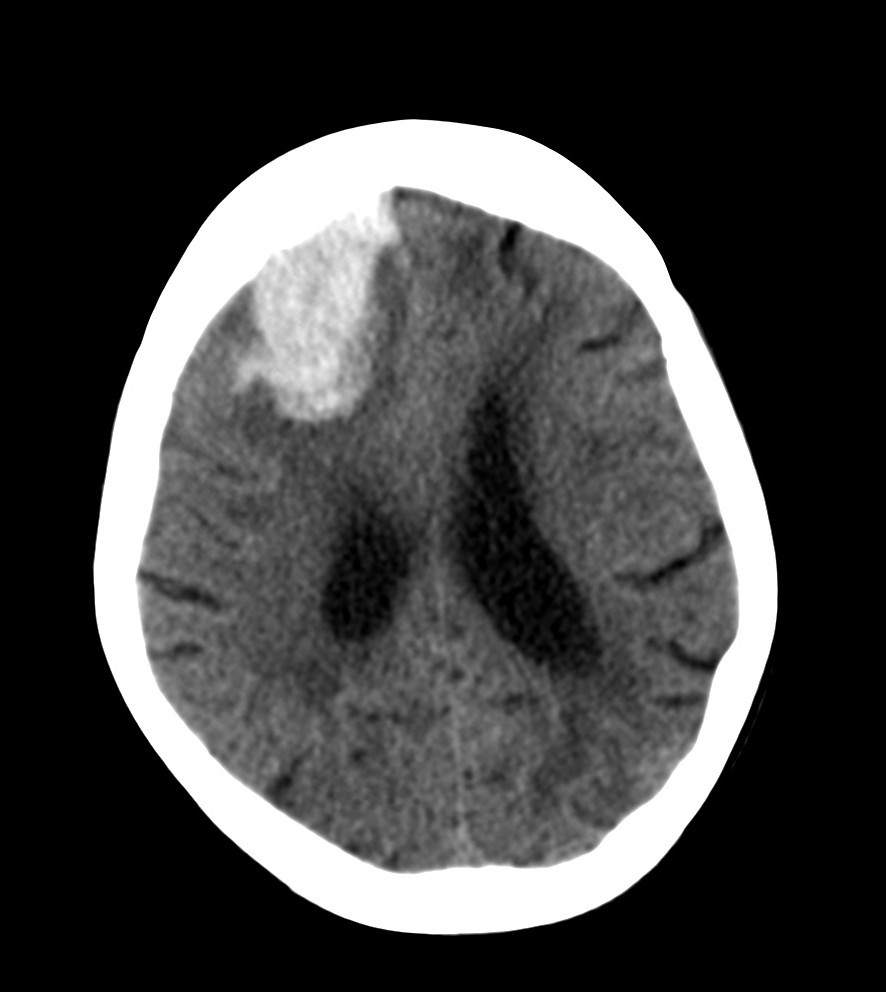

Paciente com quadro de cefaleia súbita, com déficit focal (hemiplegia ou hemiparesia), associada a HAS, bradicardia, arritmia respiratória, papiledema, sonolência, estrabismo convergente e vômitos em jato…

Diagnóstico, fator de risco principal, exame de imagem e tratamento…

HEMORRAGIA INTRAPARENQUIMATOSA

Cefaleia subita + HIC + déficit focal

TC de crânio sem contraste com hiperdensidade no parênquima

Putame: local mais atingido - hemiplegia contralateral pura

Tratamento

Suporte (HIC)… organismo reabsorve sangramento

Alvo PAs 140mmHg

Cirurgia: só opera se hematoma cerebelar >3cm (drenagem)